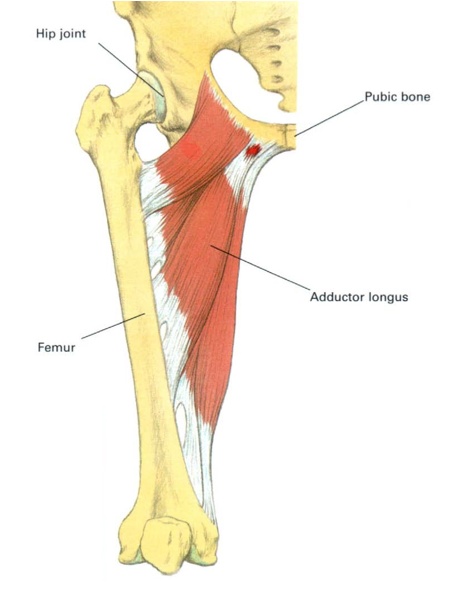

Анатомия и Функции Мышцы Adductor Magnus